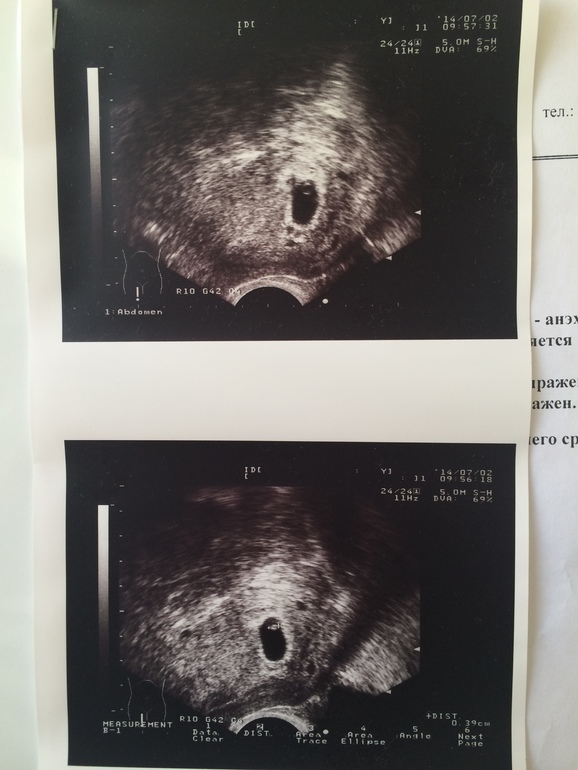

УЗИ показало, что срок 4 недели, но есть угроза и теперь я должна три дня минимум провести в постели с кучей лекарств. Конечно, я не выдержала и 2-х дней и снова пустилась в работу. А после работы мне вздумалось еще и круги по парку нарезать, гуляя пешком. И снова кровь и этот страх! И опять прием у гинеколога и УЗИ. Не повторяйте моих ошибок!!!

Сегодня настал день нашего третьего УЗИ, гинеколог назначила. Идет 9 эмбриональная и 11 акушерская недели. Конечно, у всех к этому времени только первое УЗИ случается, но у меня угроза и поэтому такой мониторинг. На УЗИ мы пошли вместе с будущим папой. Нам дали послушать биение сердца нашего малышика. Мы смогли хорошо его разглядеть. Он так смешно дергал ручками и ножками, танцевал джигу-дрыгу в моем животике))) Мужа это очень впечатлило, он еще пару раз за день потом это вспоминал и даже показывал, как он двигался! Не зря я его взяла с собой. Хотелось, чтобы наш ребенок перестал быть для него чем-то эфемерным, а перешел в разряд реального.

Итак, нам сказали, что ребенок растет и развивается очень хорошо и даже с опережением, у него длинные ноги и руки, будет высокий малыш, в папу. Угроза пока сохраняется, и я должна быть очень осторожна. Теперь меня отправили на постановку на учет, выбираю себе врача. И недели через 2 идем на 1 скрининг.

Ух, самое страшное позади, и я теперь так счастлива. Смотрю на снимок УЗИ, где уже очень хорошо все видно и понятно, и сердце заходится радостью! Я переполнена впечатлениями.